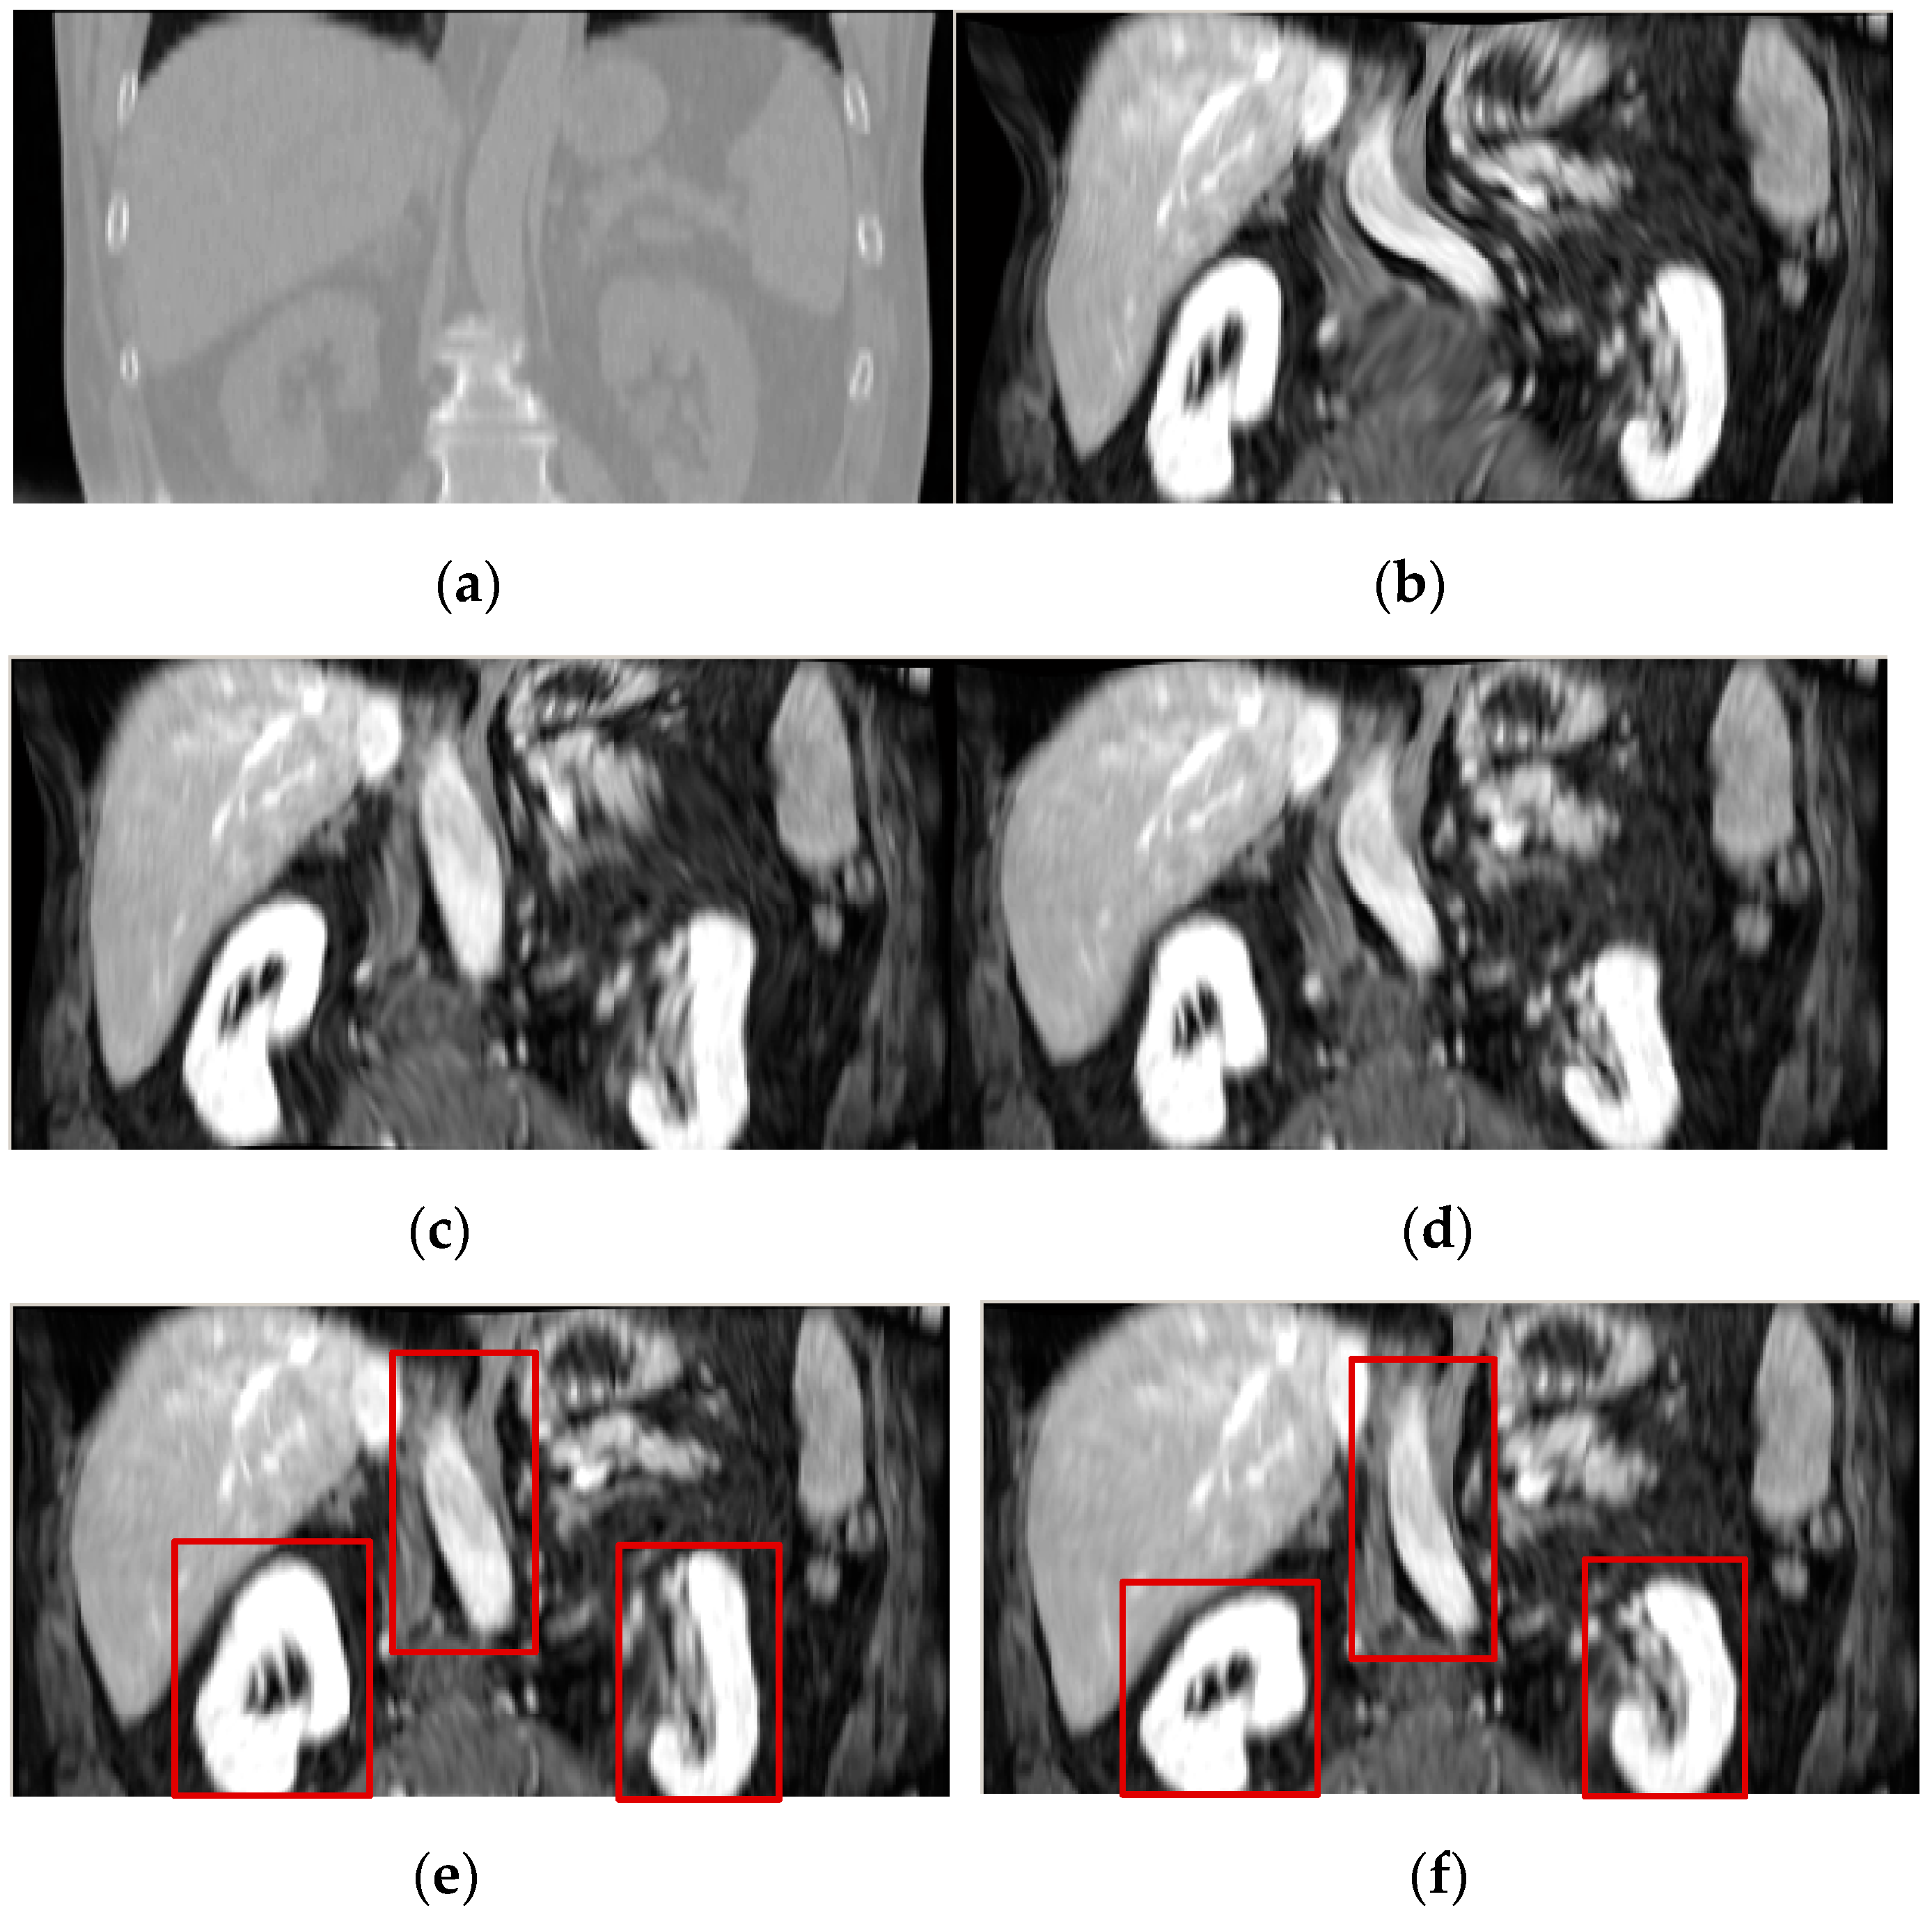

Figure 11 shows the registration results of the 3D CT-PET images for the ESSD, MIND and HLCSO, and FMIND methods. It can be observed that the ESSD and MIND methods cannot correct the deformation in the regions that are marked with the red boxes in Figure 11c,d well. By comparison, the registration results of the HLCSO and FMIND methods are more similar to the reference image shown in Figure 11a than the ESSD and MIND methods.

Figure 11.

Registration results of all evaluated methods operating on the 3D CT–PET images. (a) CT (reference image); (b) PET (float image); (c) ESSD; (d) MIND; (e) HLCSO; and, (f) FMIND.

Table 5 lists the mean and standard deviation of TRE for all evaluated methods operating on 3D CT and PET images. The comparison of TRE values shows that the HLCSO method provides the minimum mean (2.6 voxel) and standard deviation (0.7 voxel) of TRE among all the compared methods. However, the mean (2.8 voxel) and standard deviation (0.9 voxel) of TRE for the FMIND method are lower than those for the ESSD and MIND methods. The reason can be explained in this way. For the PET image, its contrast and resolution are poor and the edge features are not obvious. Therefore, the FMIND method is slightly inferior to the HLCSO method in the registration of 3D CT-PET images. However, the proposed FMIND method can still provide better structural representation results than the ESSD and MIND methods, thereby leading to its improved registration accuracy than the latter.